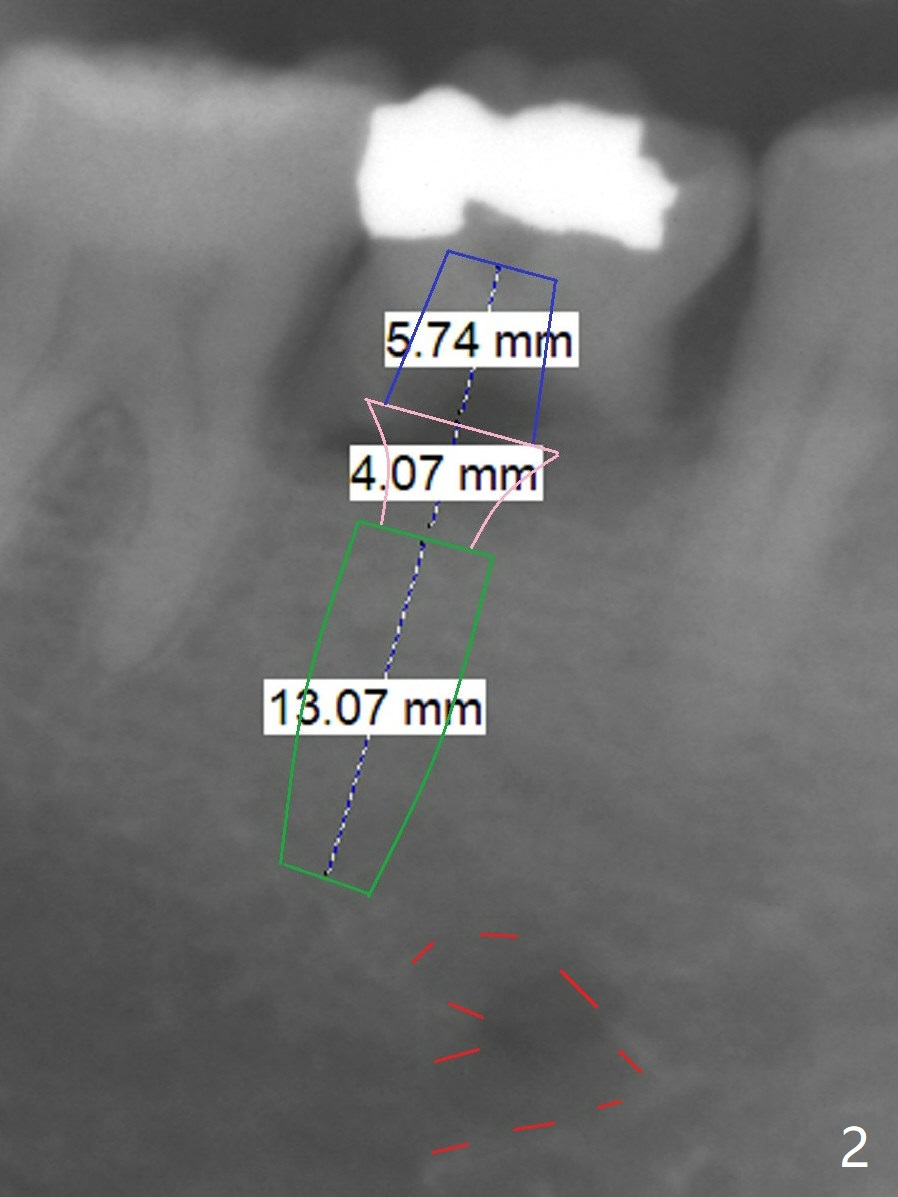

A 51-year-old man has a mobile 2nd primary molar (Fig.1 T). The latter is much wider than the 2nd premolar. Since there is crowding in the lower anterior region, it is the best to have limited orthodontic treatment to use the extra space at T to alleviate crowding anteriorly after implant osteointegration. Although the patient has no intention for orthodontics, an implant will be placed distal (Fig.2 green). To prevent periimplantitis, make sure that the implant is placed below bone. Encourage the patient to brush normally over the provisional once there is no pain. Use Rongeur to remove the septal bone before osteotomy. Try IS implants if they arrive.